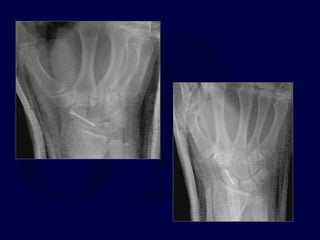

Trans-scaphoid Perilunate

Dislocations

Fix scaphoid first: dorsal

approach

Pin L-T and Mid-carpal

joints

Make sure

Radius-Lunate-

Capitate are

colinear and S-L

angle restored